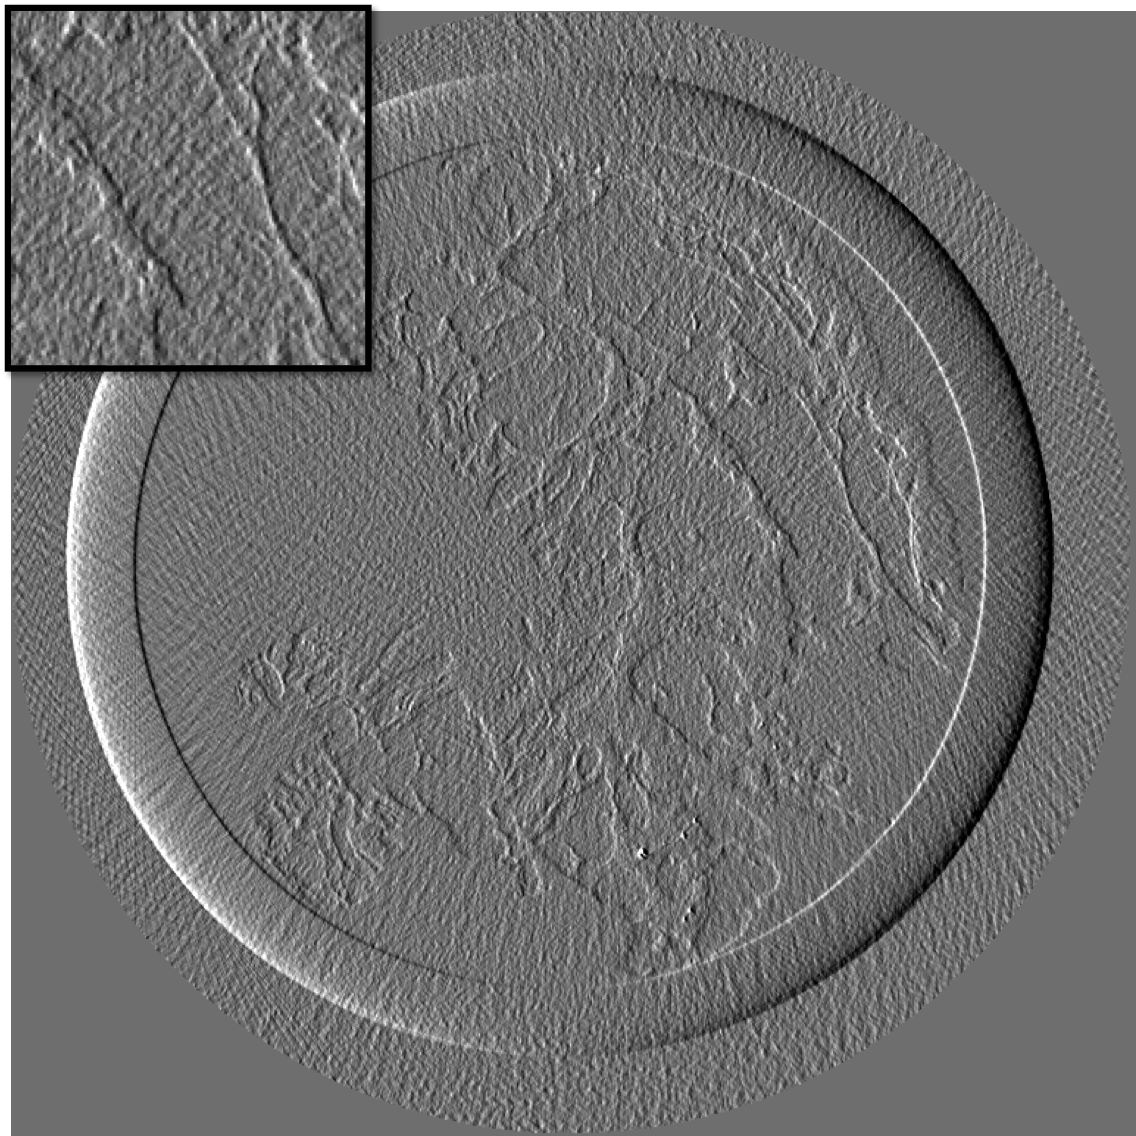

Figure 10 is the reconstruction for a pixels slice, using only 200 projections over the 1000 available. The upper left square is a zoom in the region marked in sub figure 10. The right column is the reconstruction with our method for X and Y components, while the left column is reconstructed with standard filtered back-projection using all 1000 available projections. Using our method we can still generate a high quality image with only one fifth of the projections which would be otherwise necessary to generate a high quality reconstruction with the standard FBP method. Visually the difference between the FBP results obtained with full data set and our method with a five-fold reduction of data is barely noticeable. The different borders of structures like skin layers, fatty tissues, and collagen strands are easily identified. The obtained result are very promising and a systematic evaluation for clinical application is under-way. The radiation dose absorbed by the sample during 200 projections is comparable to that of a standard clinical dual view (2D) mammography (3.5mGy).

For an eventual future clinical application of the PCI method it is important to investigate which is the acceptable compromise in terms of low dose and sufficient level of image quality. We need therefore to better explore how the quality of the reconstruction is degraded when we reduce the dose (i.e. number of projections and the acquisition time) further below the standard values. To this end, we performed a reconstruction with only 125 projections and results are shown in the figure III-D for one gradient differential image.

For an eventual future clinical application of the PCI method it is important to investigate which is the acceptable compromise in terms of low dose and sufficient level of image quality. We need therefore to better explore how the quality of the reconstruction is degraded when we reduce the dose (i.e. number of projections and the acquisition time) further below the standard values. To this end, we performed a reconstruction with only 125 projections and results are shown in the figure11. The first column present the result using our method, the second column is the result of reconstruction using FBP algorithm.

If a slightly higher noise level is tolerable, the method may be used with very few projections and thus applied to the screening and diagnosis of human breast cancers with an even lower radiation dose than conventional dual mammography. The results of our reconstruction show an image quality and a capability of discriminating fine structures that are still clinically acceptable. On the contrary, images produced with the standard FBP reconstruction method are very noisy and not diagnostically satisfactory.